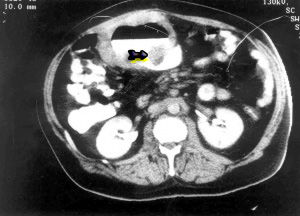

האבחנה יכולה להתבצע על-ידי בליעת בריום (תצלום 13.3), בטומוגרפיה ממוחשבת (תצלום 14.3 ו-15.3), או בגסטרוסקופיה (תמונה 9.3)